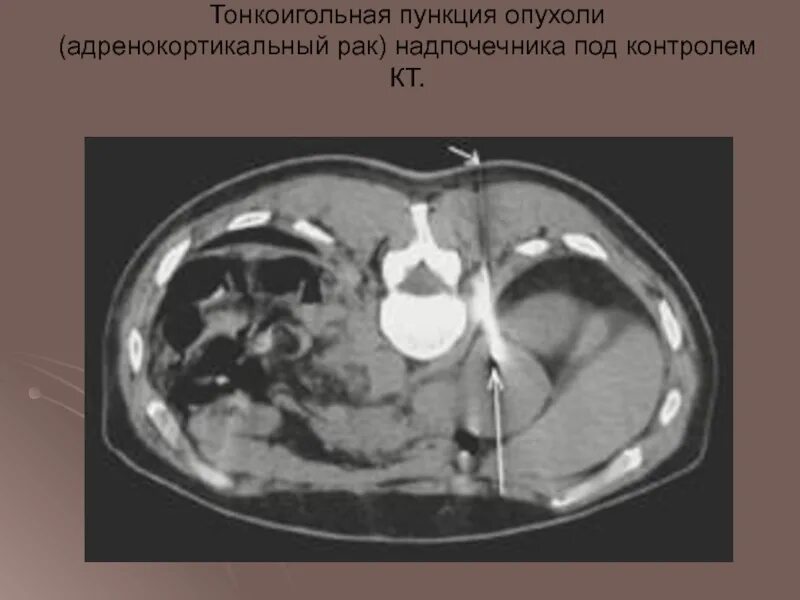

Забрюшинная онкология